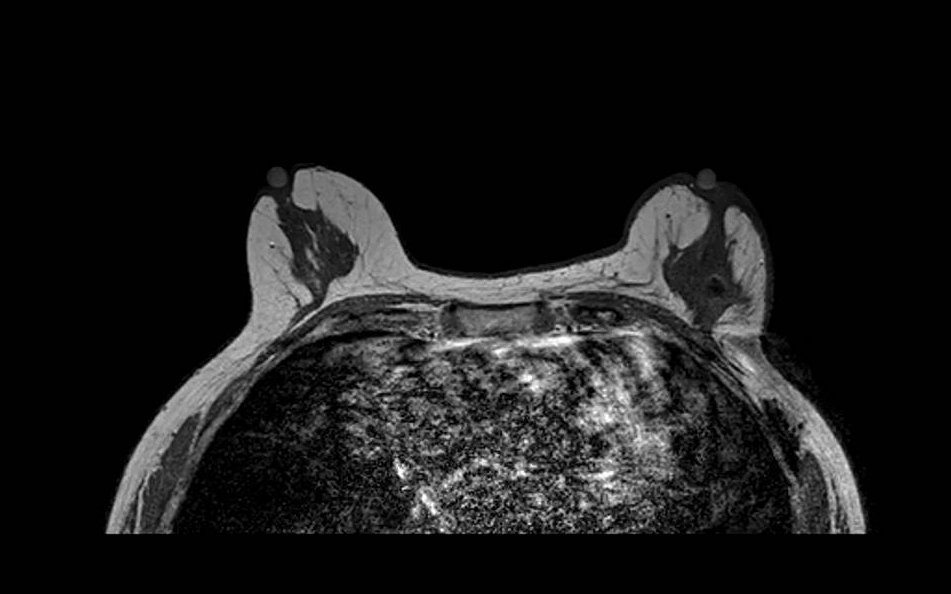

Fat Sat / B0 - T2

Bilateral asymmetric fat suppression failure on T2-weighted fat-saturated sequence. The pattern of inhomogeneous suppression differs between breasts, reflecting spatial variation in B0 across the imaging volume. Fat-saturated T2 sequences are particularly sensitive to field inhomogeneity given their longer echo times and narrower spectral selectivity.